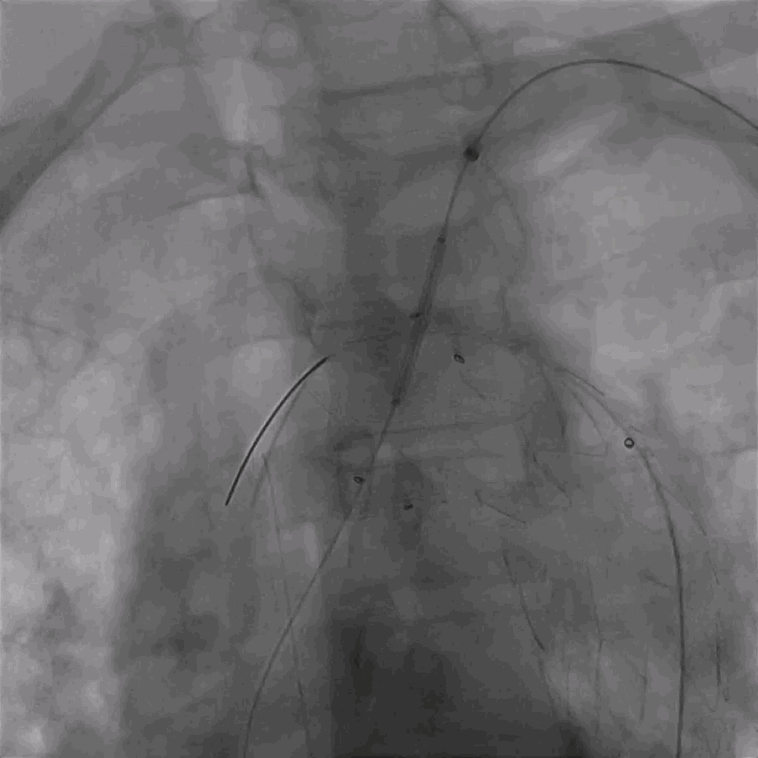

03. 左侧肱动脉采用0.035"泥鳅导丝硬头配合支撑导管顺利破膜,引入4mm球囊予以开窗处扩张。

泥鳅导丝怎么用曲乐丰教授团队:0.018"和0.035"普通泥鳅导丝行胸主动脉弓上分支原位开窗的病例分享_https://www.jmylbn.com_新闻资讯_第31张

调节支撑导管垂直于覆膜